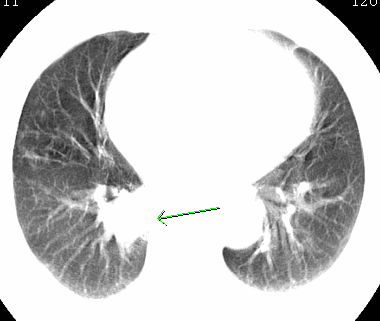

标题: CT26680:肺部右下肺静脉干结节的界定 [打印本页]

标题: CT26680:肺部右下肺静脉干结节的界定

经追查说有支扩咯血病史,但不确定

考虑1、周围型肺癌,2肺静脉畸形,前者可能大,建议增强检查。

考虑1、周围型肺癌,2肺静脉畸形,前者可能大,建议增强检查。支持!

不排除右肺下叶周围型肺癌可能。